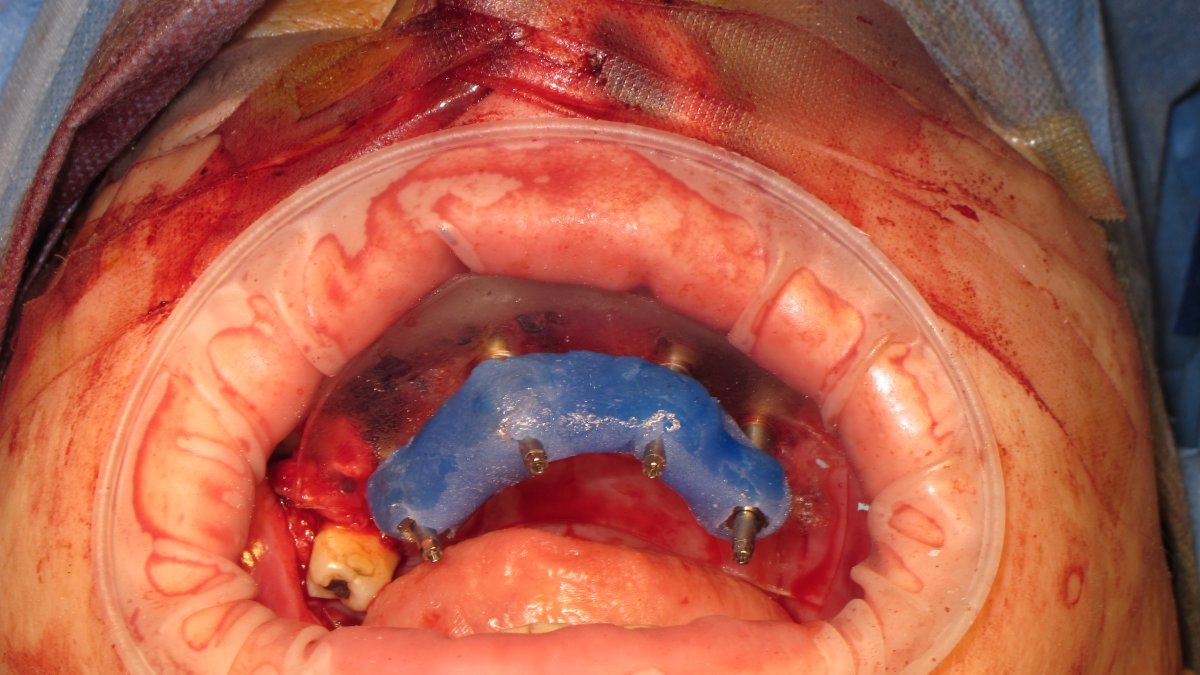

zygomatic implant placement